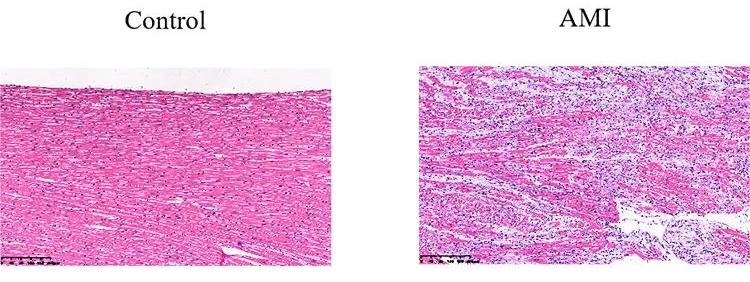

檢測指標:病理學HE染色和免疫組化分析心肌損傷。

病理HE染色示意圖